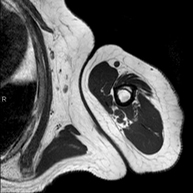

- Hip MRI

Examination for the study of injuries to tendons, muscles and hip joints. Enables early detection of hip osteoarthritis. It is very useful for detecting bursitis and dynamic osteopathy of the pubis, which is common in athletes. It lasts approximately 20 minutes. It is a radiation-free procedure.